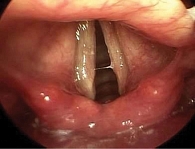

Рис. 2. Ларингоскопия, осмотр и заключение профессора К.И. Нестеровой: утолщение голосовых складок, неравномерность окраски, гиперемия и отек голосовых складок

Пациент, 34 года, с восьмилетним анамнезом изжоги, которую он купирует антацидами, альгинатами. Один-два раза в год принимает ИПП (омепразол, эзомепразол, рабепразол) курсами в течение четырех недель, а также эпизодически «по требованию». За последний год трижды проходил лечение у оториноларинголога в связи с тонзиллитом (чувство першения в горле, осиплость голоса при отсутствии заложенности носа, повышение температуры). После выполнения ларингоскопии (рис. 2) оториноларингологом были рекомендованы консультация гастроэнтеролога и эндоскопическое исследование. Проведена видеоэзофагогастродуоденоскопия (рис. 3) аппаратом экспертного класса (Olympus EVIS EXERA III  (CV-190).